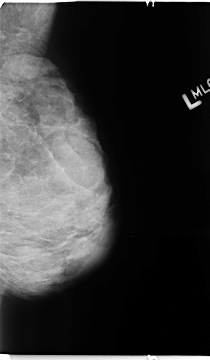

Digital Database for Screening Mammography

Volume: benign_04 Case: B-3112-1

B_3112_1.LEFT_MLO

LEFT_MLO LINES 4680 PIXELS_PER_LINE 2720 BITS_PER_PIXEL 12 RESOLUTION 50 NON_OVERLAY

FILE: B_3112_1.RIGHT_MLO.OVERLAY

TOTAL_ABNORMALITIES 1

ABNORMALITY 1

LESION_TYPE CALCIFICATION TYPE PLEOMORPHIC DISTRIBUTION REGIONAL

ASSESSMENT 4

SUBTLETY 3

PATHOLOGY BENIGN